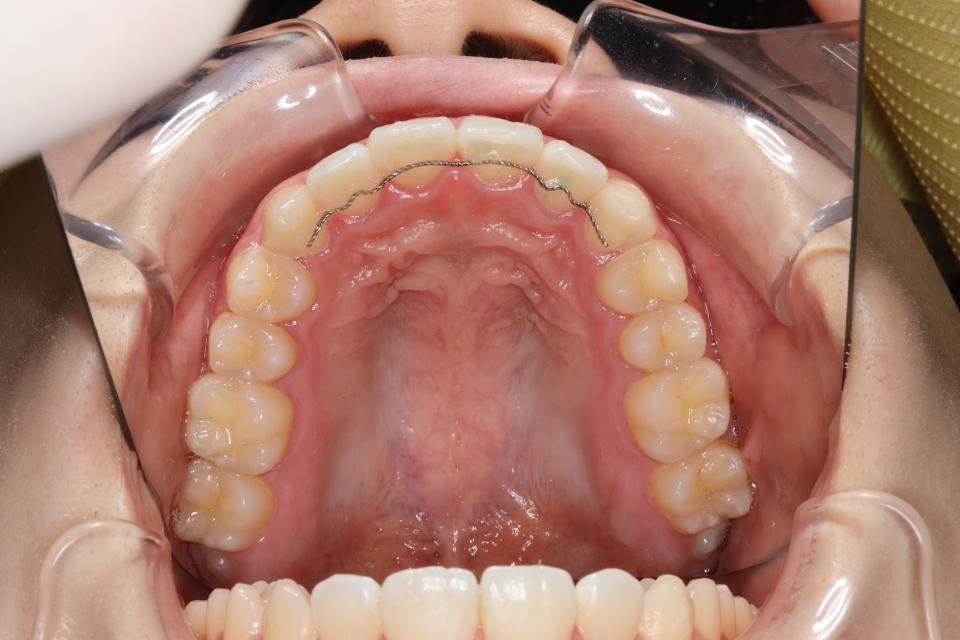

矯正治療後

20代女性の患者さんです。

上下の真ん中がズレているを気にして来院されました。

上下の歯にワイヤー(マルチブラケット装置)をつけて治療しました。

きれいに並びきるために歯のやすりがけ(IPR)も行っています。

歯並びを並べる治療は終わり、

取り外しのできる装置をはめることで後戻りの防止をして

定期的にチェックをしています。